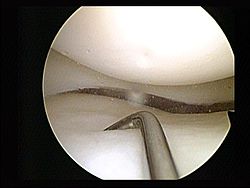

Efecto de la cirugía temprana versus terapia física sobre la función de la rodilla en pacientes con desgarros de menisco no obstructivos. Ensayo clínico aleatorizado ESCAPE

JAMA, 2 de octubre de 2018Los resultados muestran la no inferioridad de la terapia física en comparación con la cirugía temprana con meniscectomía parcial artroscópica para mejorar la función de la rodilla autoinformada en pacientes con desgarros meniscales no obstructivos.